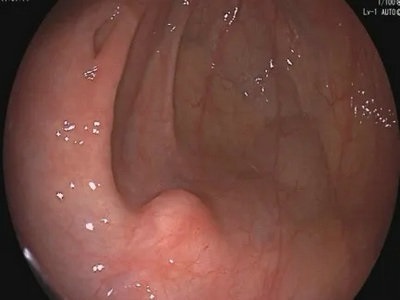

1.消化道黏膜下肿物:胃肠镜检查可以看到在黏膜上生长的病变,但如果病变长在黏膜下面,只是在黏膜下顶起一个小包,我们就需要借助超声来看看它长在哪一层、它的大小及性质,是否向胃肠道外生长等等。比如这样的:

2.消化道肿瘤:在内镜下面看到了肿瘤,但我们还需要了解这个肿瘤向下生长到了哪一层,有没有周围淋巴结的转移、有没有邻近器官的转移,对这个肿瘤进行分期,指导后续的治疗。